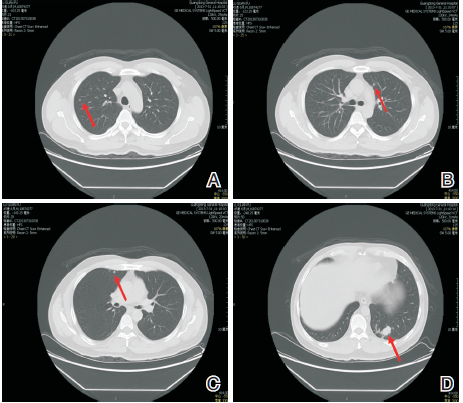

胸部CT(2013-07-31)示: 左肺下叶后基底段见一肿块影, 呈分叶状, 边缘见短毛刺, 后缘见胸膜牵拉征, 周围见少许斑片状模糊影, 增强后肿块较明显不均匀性强化, 其内可见小空泡征, 大小约22 mm× 15 mm。双肺野见多个小圆形结节影, 边界较清楚, 最大者直径约6 mm。诊断:考虑左肺下叶周围型肺癌并少许阻塞性肺炎, 建议穿刺活检; 考虑合并双肺多发转移(见图2)。

图2 胸部CT图像(2013-07-31)